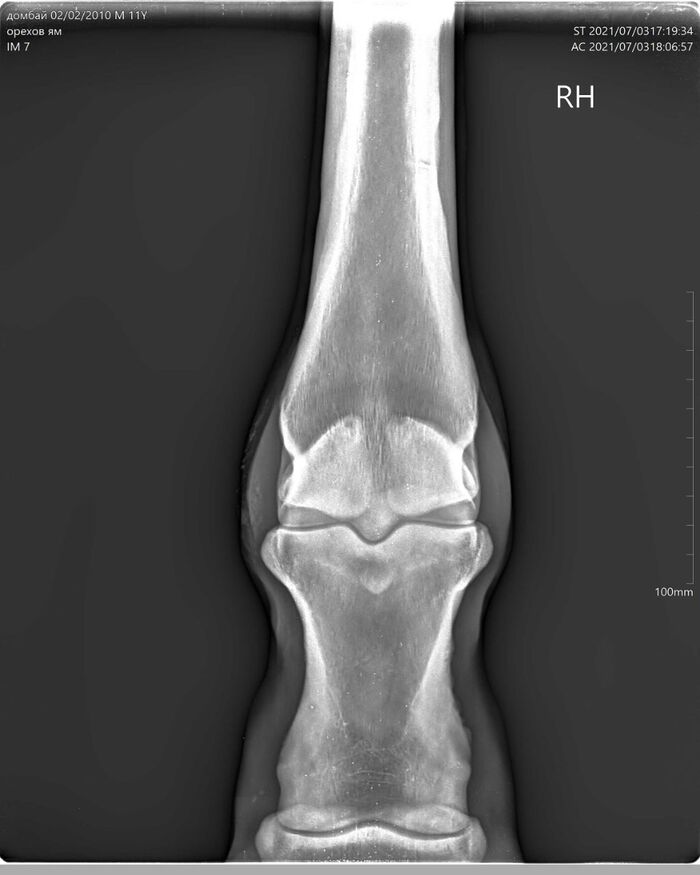

На этих x-ray снимках Домбай.

У него артроз (или артрит, я такой себе врач) пальчиков на руках.

Плюс косточка в копыте подходит очень близко к краю.